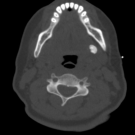

A 31-year-old woman with history of opiate use disorder (OUD) presented to her primary care physician with persistent salivary gland swelling for 1 week and a history of periodic salivary gland swelling for...